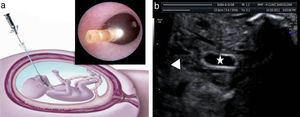

La estrategia actual se basa en la oclusión traqueal fetoscópica con balón (fetal endoscopic tracheal occlusion [FETO]) (fig. 5)45. La oclusión impide la salida del fluido pulmonar e induce un crecimiento acelerado del pulmón mediante un estímulo mecánico directo y también por la secreción de factores de crecimiento que actuarían a nivel local46. Los datos más recientes muestran que el tratamiento con oclusión traqueal fetal incrementa globalmente la supervivencia en un 35-40% respecto al pronóstico inicial47,48. La FETO con balón no es una solución definitiva, pero permite estimular el crecimiento pulmonar de forma muy marcada en un subgrupo de casos.

El balón se coloca por medio de una fetoscopia. Se procede a la intubación fetal y al acceso a la tráquea en un momento variable que puede oscilar entre las 27 y 32 semanas de gestación según la severidad del caso. Se realiza bajo anestesia regional o local en la madre y con anestesia e inmovilización fetal. Su duración media es de 17min. La duración del procedimiento está en directa relación con el riesgo de RPM y con la experiencia del grupo que la realiza. Nuestro grupo actualmente cuenta con una experiencia de más de 300 casos tratados, siendo el tiempo medio de intervención inferior a los 10min en las últimas 150 fetoscopias45,48.

Durante la fase de oclusión traqueal se recomienda que la paciente permanezca cerca del centro de referencia, ya que es necesaria una experiencia suficiente para el manejo de la vía aérea fetal. Entre 2-4 semanas más tarde, y en función de la respuesta que observemos, se retira el balón endotraqueal. Idealmente se realiza mediante una segunda fetoscopia, aunque en algunos casos puede ser necesario recurrir a la punción eco-guiada, o a la técnica ex-utero intrapartum treatment (EXIT). Con la retirada in-utero del balón se puede permitir un parto vaginal y un rápido retorno de la paciente a su unidad de referencia. Pero el argumento más importante para la retirada in-utero se deriva de estudios en ovejas donde se demuestra que se mejora de manera significativa el grado de madurez pulmonar49. Del mismo modo, existe una mayor supervivencia en los casos en que el balón fue retirado con más de 24h antes del nacimiento, lo que permite que el feto realice antes de nacer una limpieza del material contenido en tráquea y árbol respiratorio mediante movimientos respiratorios50.